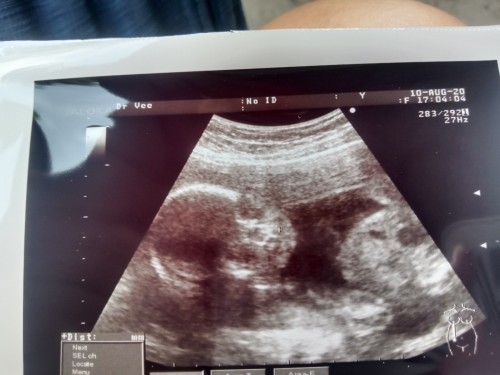

18+5week คลอด10มกรา ผู้ชายคับ♂️